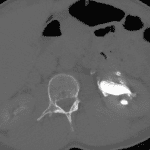

- 5 mm calcific density in the distal left ureter

- Mild left hydroureteronephrosis and perinephric stranding

- Small amount of fluid in the left perinephric space and left paracolic gutter

- Excretory phase images show evidence of forniceal rupture with pyelosinus reflux

- Obstructing ureteral calculus

Obstructing 5 mm distal left ureteral calculus with resultant mild left hydroureteronephrosis and evidence of forniceal rupture on excretory phase images.